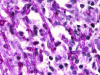

Scedosporium spp. are increasingly recognized as causes of resistant life-threatening infections in immunocompromised patients. Scedosporium spp. also cause a wide spectrum of conditions, including mycetoma, saprobic involvement and colonization of the airways, sinopulmonary infections, extrapulmonary localized infections, and disseminated infections. Invasive scedosporium infections are also associated with central nervous infection following near-drowning accidents. The most common sites of infection are the lungs, sinuses, bones, joints, eyes, and brain. Scedosporium apiospermum and Scedosporium prolificans are the two principal medically important species of this genus. Pseudallescheria boydii, the teleomorph of S. apiospermum, is recognized by the presence of cleistothecia. Recent advances in molecular taxonomy have advanced the understanding of the genus Scedosporium and have demonstrated a wider range of species than heretofore recognized. Studies of the pathogenesis of and immune response to Scedosporium spp. underscore the importance of innate host defenses in protection against these organisms. Microbiological diagnosis of Scedosporium spp. currently depends upon culture and morphological characterization. Molecular tools for clinical microbiological detection of Scedosporium spp. are currently investigational. Infections caused by S. apiospermum and P. boydii in patients and animals may respond to antifungal triazoles. By comparison, infections caused by S. prolificans seldom respond to medical therapy alone. Surgery and reversal of immunosuppression may be the only effective therapeutic options for infections caused by S. prolificans.